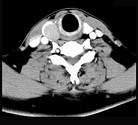

问题 男,43岁,因右颈部扪及一包块来院就诊。如图所示该患者应诊断为 ( )

选项 A、甲状腺原发淋巴瘤 B、甲状腺转移瘤 C、甲状腺腺癌 D、结节性甲状腺肿 E、甲状腺腺瘤

答案 E